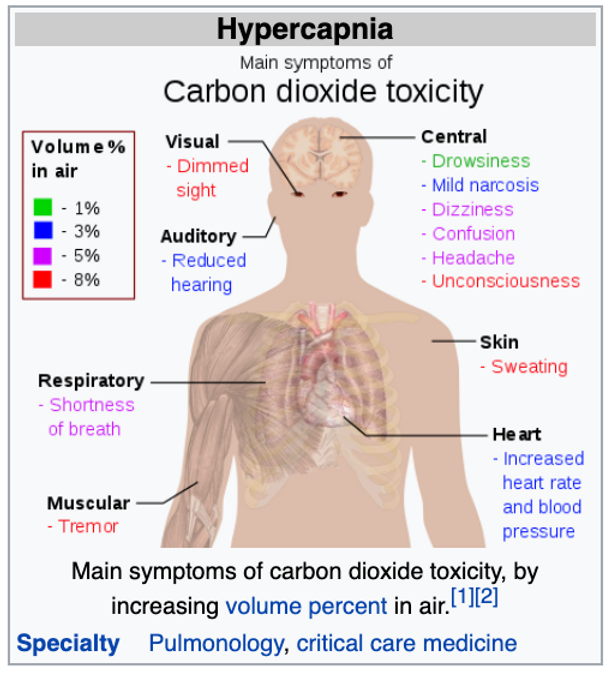

31) Hypercapnia

2) Carbon dioxide, carbon monoxide and methane gas poisoning from air-pollution and wearing masks..[19][20][21][22][23][24]